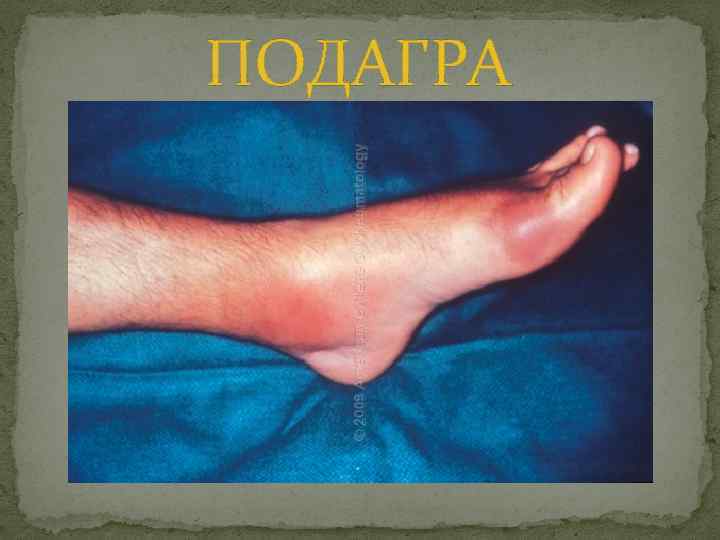

ПОДАГРА

ПОДАГРА

Закрути тиски как можно туже – получится ревматизм, а теперь сделайте еще один оборот – получится подагра. Неизвестный автор В переводе с латинского подагра означает «огонь в стопе»

Закрути тиски как можно туже – получится ревматизм, а теперь сделайте еще один оборот – получится подагра. Неизвестный автор В переводе с латинского подагра означает «огонь в стопе»

Острый подагрический артрит Основным клиническим проявлением подагры является острый, начинающийся внезапно артрит, характеризующийся быстро нарастающей сильнейшей болью, гиперемией и гипертермией, протекающий в большинстве случаев по типу моноартрита.

Острый подагрический артрит Основным клиническим проявлением подагры является острый, начинающийся внезапно артрит, характеризующийся быстро нарастающей сильнейшей болью, гиперемией и гипертермией, протекающий в большинстве случаев по типу моноартрита.

Более чем в половине случаев в дебюте заболевания поражается первый плюснефаланговый сустав, реже – суставы плюсны, коленный и г/с суставы.

Более чем в половине случаев в дебюте заболевания поражается первый плюснефаланговый сустав, реже – суставы плюсны, коленный и г/с суставы.